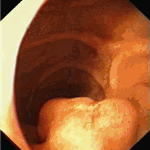

Gastrinoma (MEN-I – multiple endocrine neoplasia I). Irregular ball-shaped tumour in duodenum in a 37-year old man. Mucosa on its surface is intact.